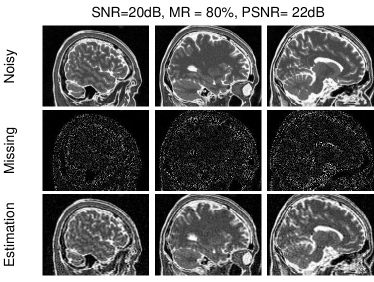

Model Objective Constraints PCA min𝐀,𝐁𝐘𝐀𝐁F2subscript𝐀𝐁superscriptsubscriptnorm𝐘superscript𝐀𝐁top𝐹2\min_{\mathbf{A},\;\mathbf{B}}\;\left\|\mathbf{Y}-\mathbf{A}\mathbf{B}^{\top}\right\|_{F}^{2} 𝐀𝐀=𝐈superscript𝐀top𝐀𝐈\mathbf{A}^{\top}\mathbf{A}=\mathbf{I} RPCA [95] min𝐗,𝐄𝐗+λ𝐄1subscript𝐗𝐄subscriptnorm𝐗𝜆subscriptnorm𝐄1\min_{\mathbf{X},\;\mathbf{E}}\;\left\|\mathbf{X}\right\|_{*}+\lambda\left\|\mathbf{E}\right\|_{1} 𝐘=𝐗+𝐄𝐘𝐗𝐄\mathbf{Y}=\mathbf{X+E}, 𝐗=𝐀𝐁𝐗superscript𝐀𝐁top\mathbf{X}=\mathbf{A}\mathbf{B}^{\top} RPCA on graphs [97] min𝐗,𝐄𝐗+λ𝐄1+γtrace(𝐗𝚽𝐗)subscript𝐗𝐄subscriptnorm𝐗𝜆subscriptnorm𝐄1𝛾trace𝐗𝚽superscript𝐗top\min_{\mathbf{X},\;\mathbf{E}}\;\left\|\mathbf{X}\right\|_{*}+\lambda\;\left\|\mathbf{E}\right\|_{1}+\gamma\;\text{trace}(\mathbf{X}\mathbf{\Phi}\mathbf{X}^{\top}) 𝐘=𝐗+𝐄𝐘𝐗𝐄\mathbf{Y}=\mathbf{X+E}, 𝐗=𝐀𝐁𝐗superscript𝐀𝐁top\mathbf{X}=\mathbf{A}\mathbf{B}^{\top} Graph Laplacian PCA (GLPCA) [101] min𝐀,𝐁𝐘𝐀𝐁F2+γtrace(𝐁𝚽𝐁)subscript𝐀𝐁superscriptsubscriptnorm𝐘superscript𝐀𝐁top𝐹2𝛾tracesuperscript𝐁top𝚽𝐁\min_{\mathbf{A},\;\mathbf{B}}\;\left\|\mathbf{Y}-\mathbf{A}\mathbf{B}^{\top}\right\|_{F}^{2}+\gamma\;\text{trace}(\mathbf{B}^{\top}\mathbf{\Phi}\mathbf{B}) 𝐁𝐁=𝐈superscript𝐁top𝐁𝐈\mathbf{B}^{\top}\mathbf{B}=\mathbf{I} Robust GLPCA [101] min𝐀,𝐁𝐘𝐀𝐁2,1+γtrace(𝐁𝚽𝐁)subscript𝐀𝐁subscriptnorm𝐘superscript𝐀𝐁top21𝛾tracesuperscript𝐁top𝚽𝐁\min_{\mathbf{A},\;\mathbf{B}}\;\left\|\mathbf{Y}-\mathbf{A}\mathbf{B}^{\top}\right\|_{2,1}+\gamma\;\text{trace}(\mathbf{B}^{\top}\mathbf{\Phi}\mathbf{B}) 𝐁𝐁=𝐈superscript𝐁top𝐁𝐈\mathbf{B}^{\top}\mathbf{B}=\mathbf{I} NMF [26] min𝐀,𝐁𝐘𝐀𝐁F2subscript𝐀𝐁superscriptsubscriptnorm𝐘superscript𝐀𝐁top𝐹2\min_{\mathbf{A},\;\mathbf{B}}\;\left\|\mathbf{Y}-\mathbf{A}\mathbf{B}^{\top}\right\|_{F}^{2} 𝐀𝐀\mathbf{A} and 𝐁𝐁\mathbf{B} are nonnegative Orthogonal NMF [32, 33] min𝐀,𝐁𝐘𝐀𝐁F2subscript𝐀𝐁superscriptsubscriptnorm𝐘superscript𝐀𝐁top𝐹2\min_{\mathbf{A},\;\mathbf{B}}\;\left\|\mathbf{Y}-\mathbf{A}\mathbf{B}^{\top}\right\|_{F}^{2} 𝐀𝐀\mathbf{A} and 𝐁𝐁\mathbf{B} are nonnegative, and 𝐁𝐁=𝐈superscript𝐁top𝐁𝐈\mathbf{B}^{\top}\mathbf{B}=\mathbf{I} Sparse component analysis min𝐀,𝐁𝐘𝐀𝐁F2+λ𝐁1subscript𝐀𝐁superscriptsubscriptnorm𝐘superscript𝐀𝐁top𝐹2𝜆subscriptnorm𝐁1\min_{\mathbf{A},\;\mathbf{B}}\;\left\|\mathbf{Y}-\mathbf{A}\mathbf{B}^{\top}\right\|_{F}^{2}+\lambda\left\|\mathbf{B}\right\|_{1} Various constraints, e.g. nonnegativity Smooth component analysis (SmCA) [34] min𝐀,𝐁𝐗𝐀𝐁F2+γ1𝐋1𝐀2,1+γ2𝐋2𝐁2,1subscript𝐀𝐁superscriptsubscriptnorm𝐗superscript𝐀𝐁top𝐹2subscript𝛾1subscriptnormsubscript𝐋1𝐀21subscript𝛾2subscriptnormsubscript𝐋2𝐁21\min_{\mathbf{A},\mathbf{B}}\left\|\mathbf{X}-\mathbf{A}\mathbf{B}^{\top}\right\|_{F}^{2}+\gamma_{1}\left\|\mathbf{L}_{1}\mathbf{A}\right\|_{2,1}+\gamma_{2}\left\|\mathbf{L}_{2}\mathbf{B}\right\|_{2,1} Various constraints, e.g., nonnegativity. 𝐋1,𝐋2subscript𝐋1subscript𝐋2\mathbf{L}_{1},\mathbf{L}_{2} represent difference operators.

5 Dimensionality Reduction for Incomplete Data Corrupted by Outliers

When we are ready to apply any specific method we have discussed to real-world problems, several practical issues arise. These include questions such as to how many latent components one should extract, and how to remove the noise and outliers from noisy and/or incomplete observation data. Particularly, multi-block high-order data may cause data deluge and pose new challenges for effective and efficient data analysis. A common approach to deal with these issues is dimensionality reduction, which has been a ubiquitous technique broadly applied for noise reduction, data compression, and feature extraction. Indeed, most models and algorithms we discussed above rely on efficient and robust dimensionality reduction.

The key to achieve dimensionality reduction is the low-rank nature of data that is essentially related to the complexity of the generative model. Estimating this rank, or equivalently, the number of latent components, is often a challenging task and referred to as the model selection problem. As an example, in brain data imaging we never know how many latent sources that contribute essentially to the measured data; different model order selections may lead to quite different latent components and, consequently, different interpretations.